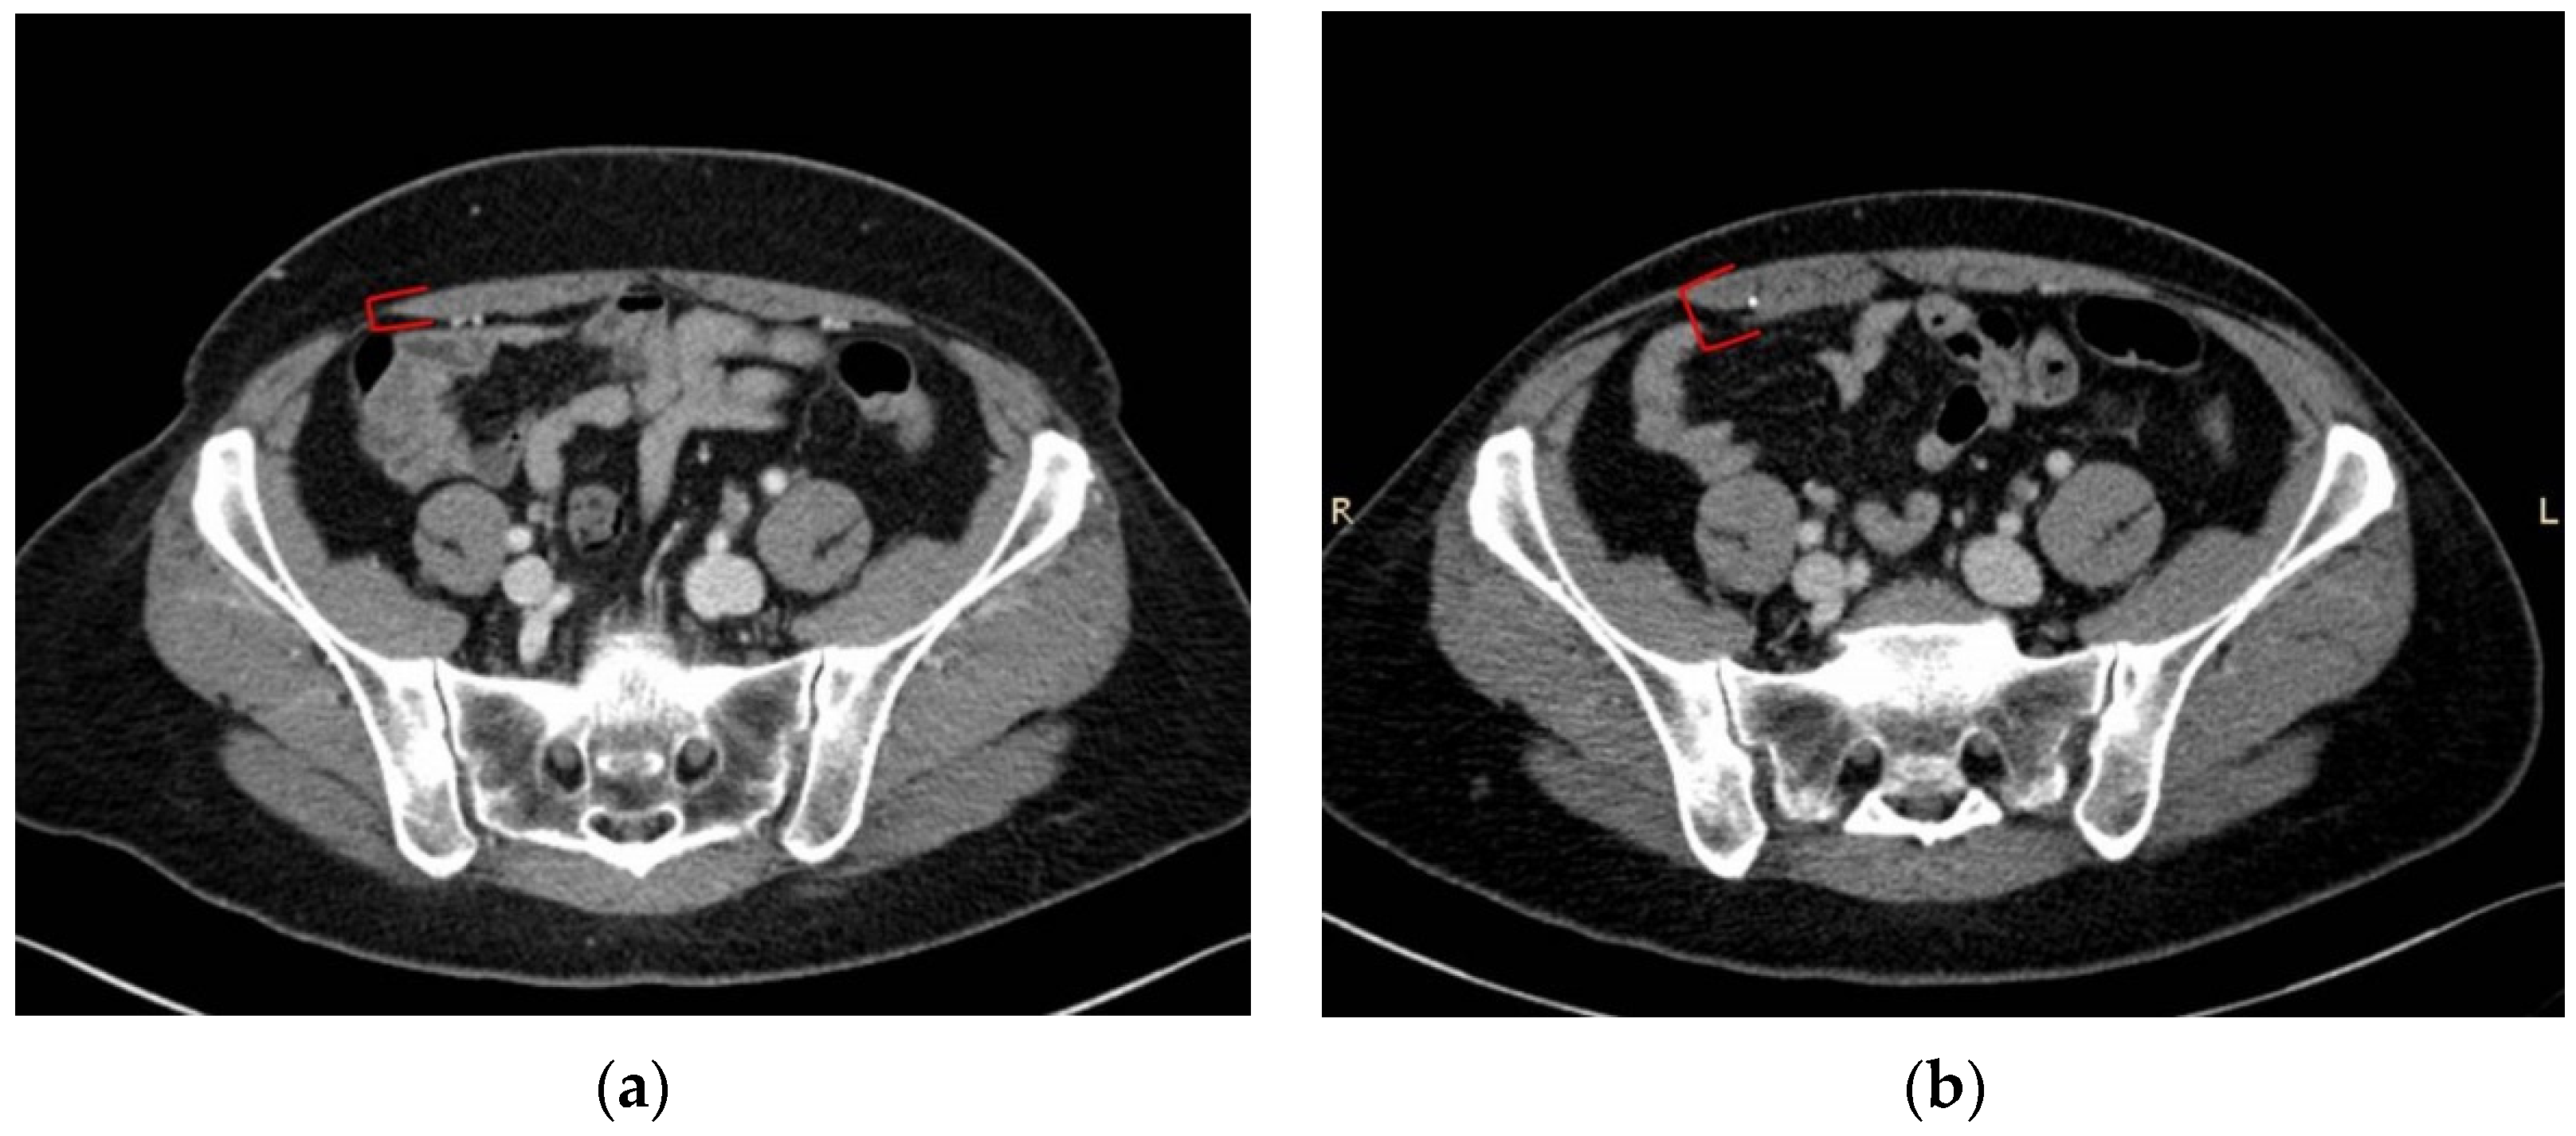

3.2. Muscle Quality Assessment